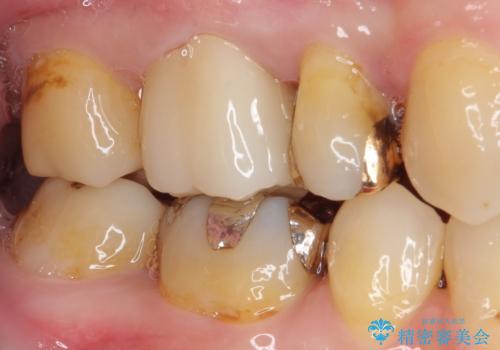

- 奥歯の裏側がしみるとのことで来院された患者様です。

矯正治療による歯肉退縮がおき、歯根にまで虫歯が波及していました。

虫歯が大きかったため、フルジルコニアクラウンにて補綴することとしました。

一部歯肉の中にまで虫歯が波及しており、汚れが溜まりやすくなっていましたが、クラウン装着後は汚れが溜まることはなくなりました。

しみていた症状もなくなり、患者様には大変満足していただきました。